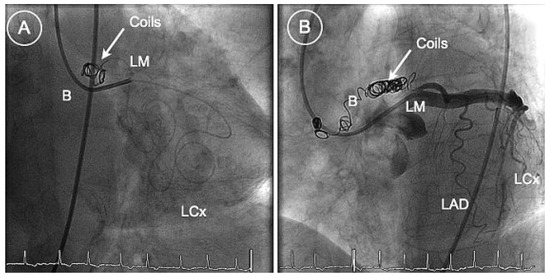

Platinum Reward for Theft, or the Percutaneous Treatment of Coronary Steal Due to a Giant Coronary Artery Fistula

An 89-year-old sister who presented with angina pectoris and signs of acute left ventricular failure had a history of chronic dyspnoea aggravated a few days prior to admission by orthopnoea and nycturia. [...] Full article